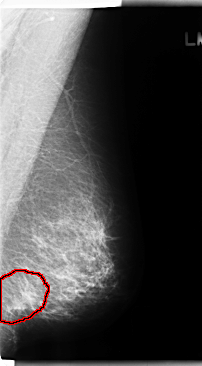

C_0215_1.LEFT_MLO

LEFT_MLO LINES 4752 PIXELS_PER_LINE 2624 BITS_PER_PIXEL 12 RESOLUTION 50 OVERLAY

FILE: C_0215_1.LEFT_MLO.OVERLAY

TOTAL_ABNORMALITIES 1

ABNORMALITY 1

LESION_TYPE MASS SHAPE IRREGULAR MARGINS ILL_DEFINED

ASSESSMENT 5

SUBTLETY 5

PATHOLOGY MALIGNANT

TOTAL_OUTLINES 1

BOUNDARY